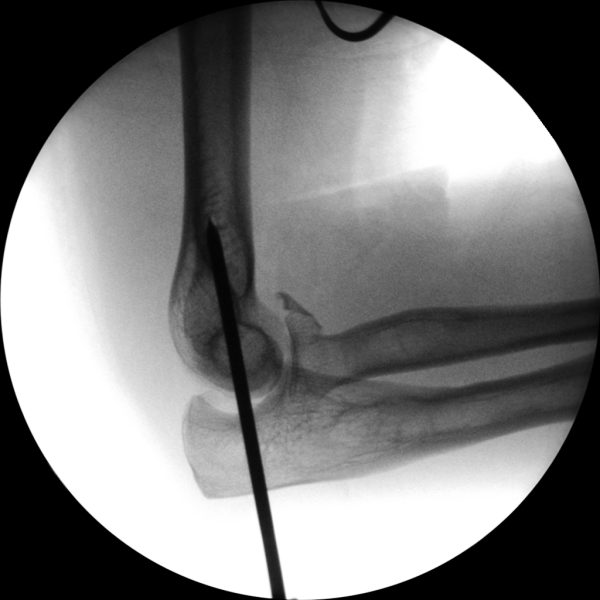

Skan-C plays a critical role in orthopaedic procedures, providing excellent imaging during interventional procedures, and allowing for precise localization and accurate treatment. The ability of Skan-C to offer dynamic visualization of visualization structures enhances patient safety, minimizes complications, and improves the overall effectiveness of orthopedic interventions.

Orthopedic procedures in which Skan-C is highly effective are

CRIF - Closed reduction internal fixation

ORIF - Open reduction internal fixation